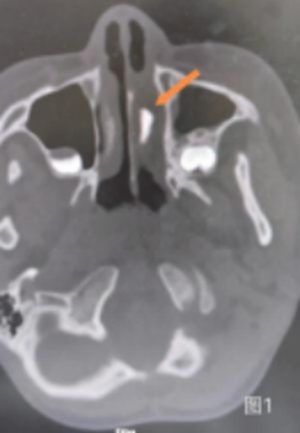

立即為小帥完善了

鼻竇CT檢查

結(jié)果提示

左側(cè)鼻腔可見高密度影

鼻腔異物可能性非常大